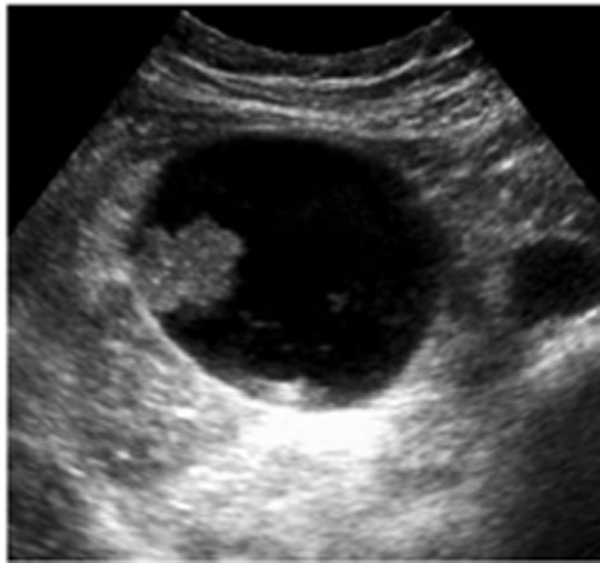

Pancreatic Psydocyst

Spherical fluid collection of pancreatic enzymes that arise from inflamatory, necrotic and hemorrhage processes of the pancrreas

persistently elevated amylase and lipase

Pancreatic Psydocyst

Spherical fluid collection of pancreatic enzymes that arise from inflamatory, necrotic and hemorrhage processes of the pancrreas

persistently elevated amylase and lipase

Pancreatic Psydocyst

Spherical fluid collection of pancreatic enzymes that arise from inflamatory, necrotic and hemorrhage processes of the pancrreas